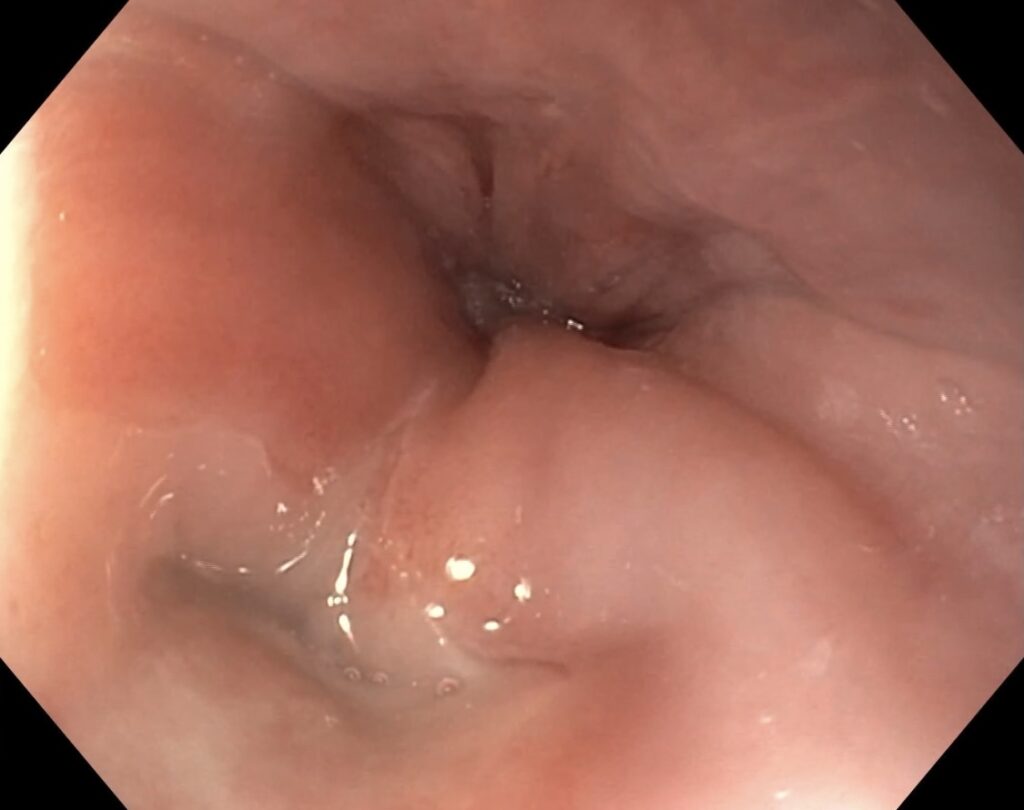

Persistierende Dysphagie bei Zenkerschem Divertikel einer 90-jährigen Patientin.

Nach Einlage einer Magensonde kann mit einem Elektromesser das Septum zwischen Ösophaguslumen und Divertikel gespalten werden. Dabei erfolgt die Myotomie des M. cricopharyngeus. Das Divertikel kollabiert folglich nach ventral, eine Nahrungspassage ist somit wieder möglich.